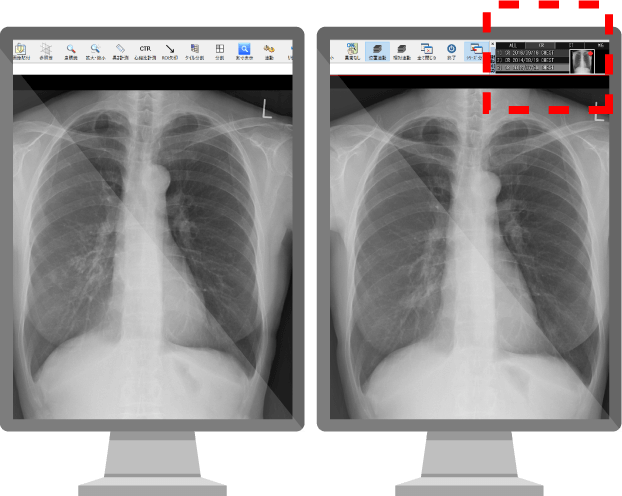

健診読影にAIを活用したい!

- 各メーカーのAIサービスと連携し、読影をサポート

- AIが肺結節影などの陰影を検出し、ビューア上に表示

- 陰影を検出した検査は、画像解析結果の確認を促す機能を搭載

撮影画像

AI解析画像

不安や悩む時間を軽減し、見逃しを防ぐ。

肺所見の指摘数の増加も見込めます!